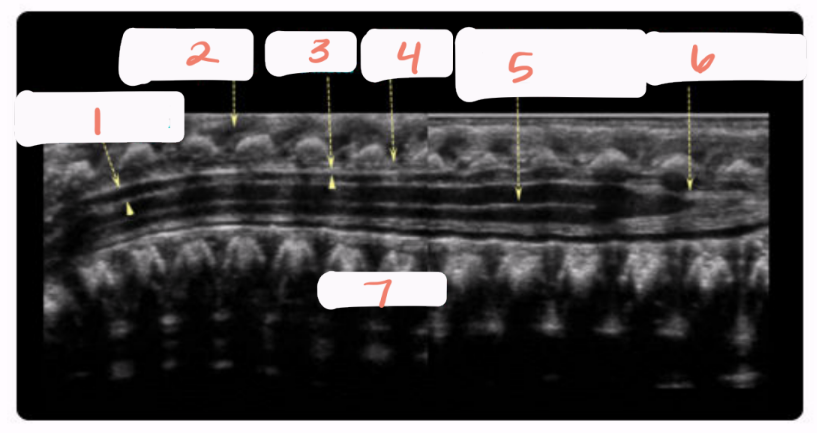

1

spinal cord

2

subarachnoid space

3

arachnoid and dura mater

4

cartilaginous spinous process

5

conus medullaris

6

central echo complex in hypoechoic spinal cord

7

vertebral bodies

8

nerve roots forming the cauda equina